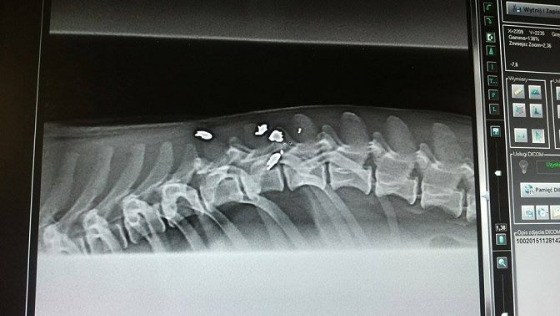

Po konsultacji z lekarzem prowadzącym Michasia zdecydowaliśmy, że podejmiemy próbę leczenia przy użyciu komórek macierzystych. Lekarze użyją ich do ostrzyknięcia pęcherza moczowego. Jest szansa, iż komórki pomogą psiakowi w samodzielnym oddawaniu moczu. Zamówiliśmy je z Warszawy i będą na czwartek rano. Wtedy lekarze wykonają dwa zabiegi ( usunięcie wodonercza i ostrzyknięcie pęcherza) wykorzystując jedno znieczulenie dla dobra Michasia.